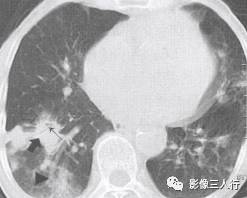

非典型肺炎的CT征象特点:分布不均匀、形态不同、大小不一的肺实变是本组 患者共同存在的基本CT表现。肺实变通常由于肺泡内充盈浆液性、渗出性或血性液 体、炎细胞或其他成分,导致肺实质弥漫性或局灶性密度增高。早期表现为边界不 清楚的0.5〜1.0cm的结节性高密度灶,随着病变的进展,融合成团块或斑片状阴 影,掩盖肺血管纹理。较大的实变影像内可见支气管分支的透亮影则为空气支气管征。见图9。